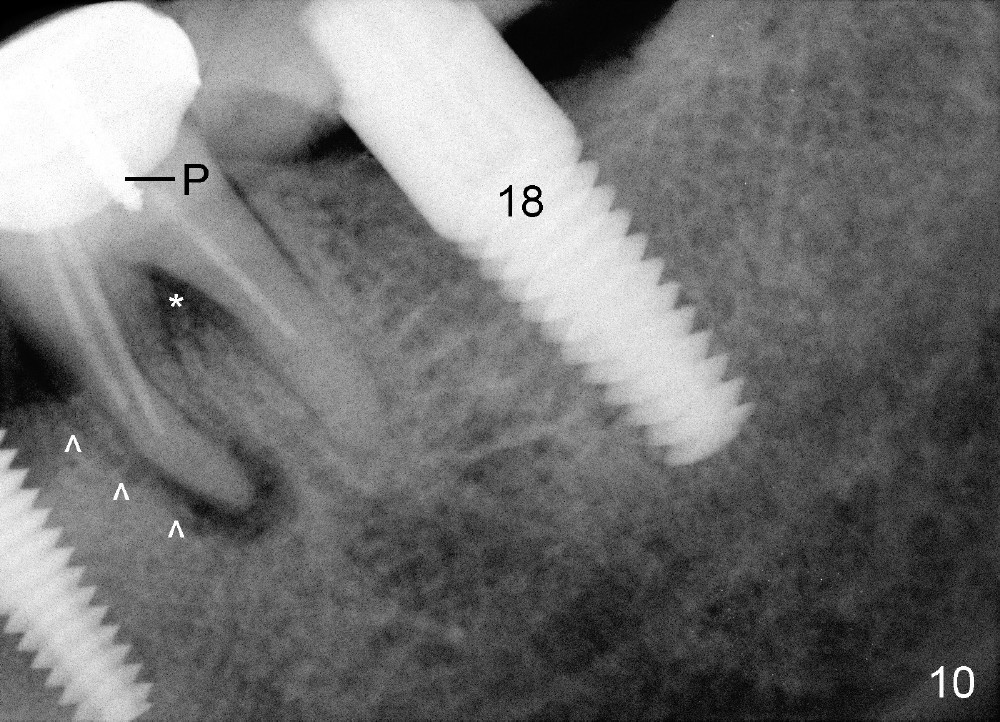

Four and a half months later, an implant is planned for #18 (Fig.7). The preop PA reveals that there is no bone growth around the implant at the site of #20, although the buccal swelling appears less prominent (Fig.8) than before (Fig.5). Without too much thinking, flap is raised for debridement (Fig.9). Autogenous bone graft is harvested from the site of #18 and placed in the defect area. By the time the surgery is done, the possible source becomes obvious: the periapical infection of the mesial root of #19 (Fig.10 arrowheads from primary infection to secondary one). Since there is also a furca lesion, possibly related to the post (P), the tooth has guarded to poor prognosis.